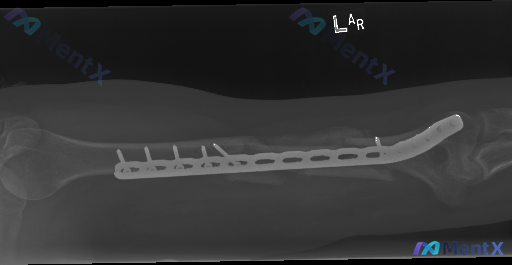

整理到一例左肱骨骨折内固定术后的复查影像资料,先把关键信息列出来,大家帮忙看看这种情况更往哪边考虑: 病例背景 左肱骨干骨折内固定术后复查(具体术后时间未明确说明)。 影像表现(左上臂+胸部X光) 1. 内固定情况:左肱骨外侧可见锁定加压接骨板及多枚螺钉固定,钢板、螺钉在位,未见明显松动、退出或断裂...

整理到一份左肱骨干骨折内固定术后的影像资料,大家可以先看一下关键表现: 基本背景:左肱骨干骨折术后复查 影像核心表现: - 肱骨外侧可见锁定加压钢板及多枚螺钉固定 - 钢板中段下方骨折区域,皮质不连续,断端存在分离及错位 - 断端周围有模糊、密度增高的骨痂形成迹象,但部分区域断端间隙仍可见,骨质连接...